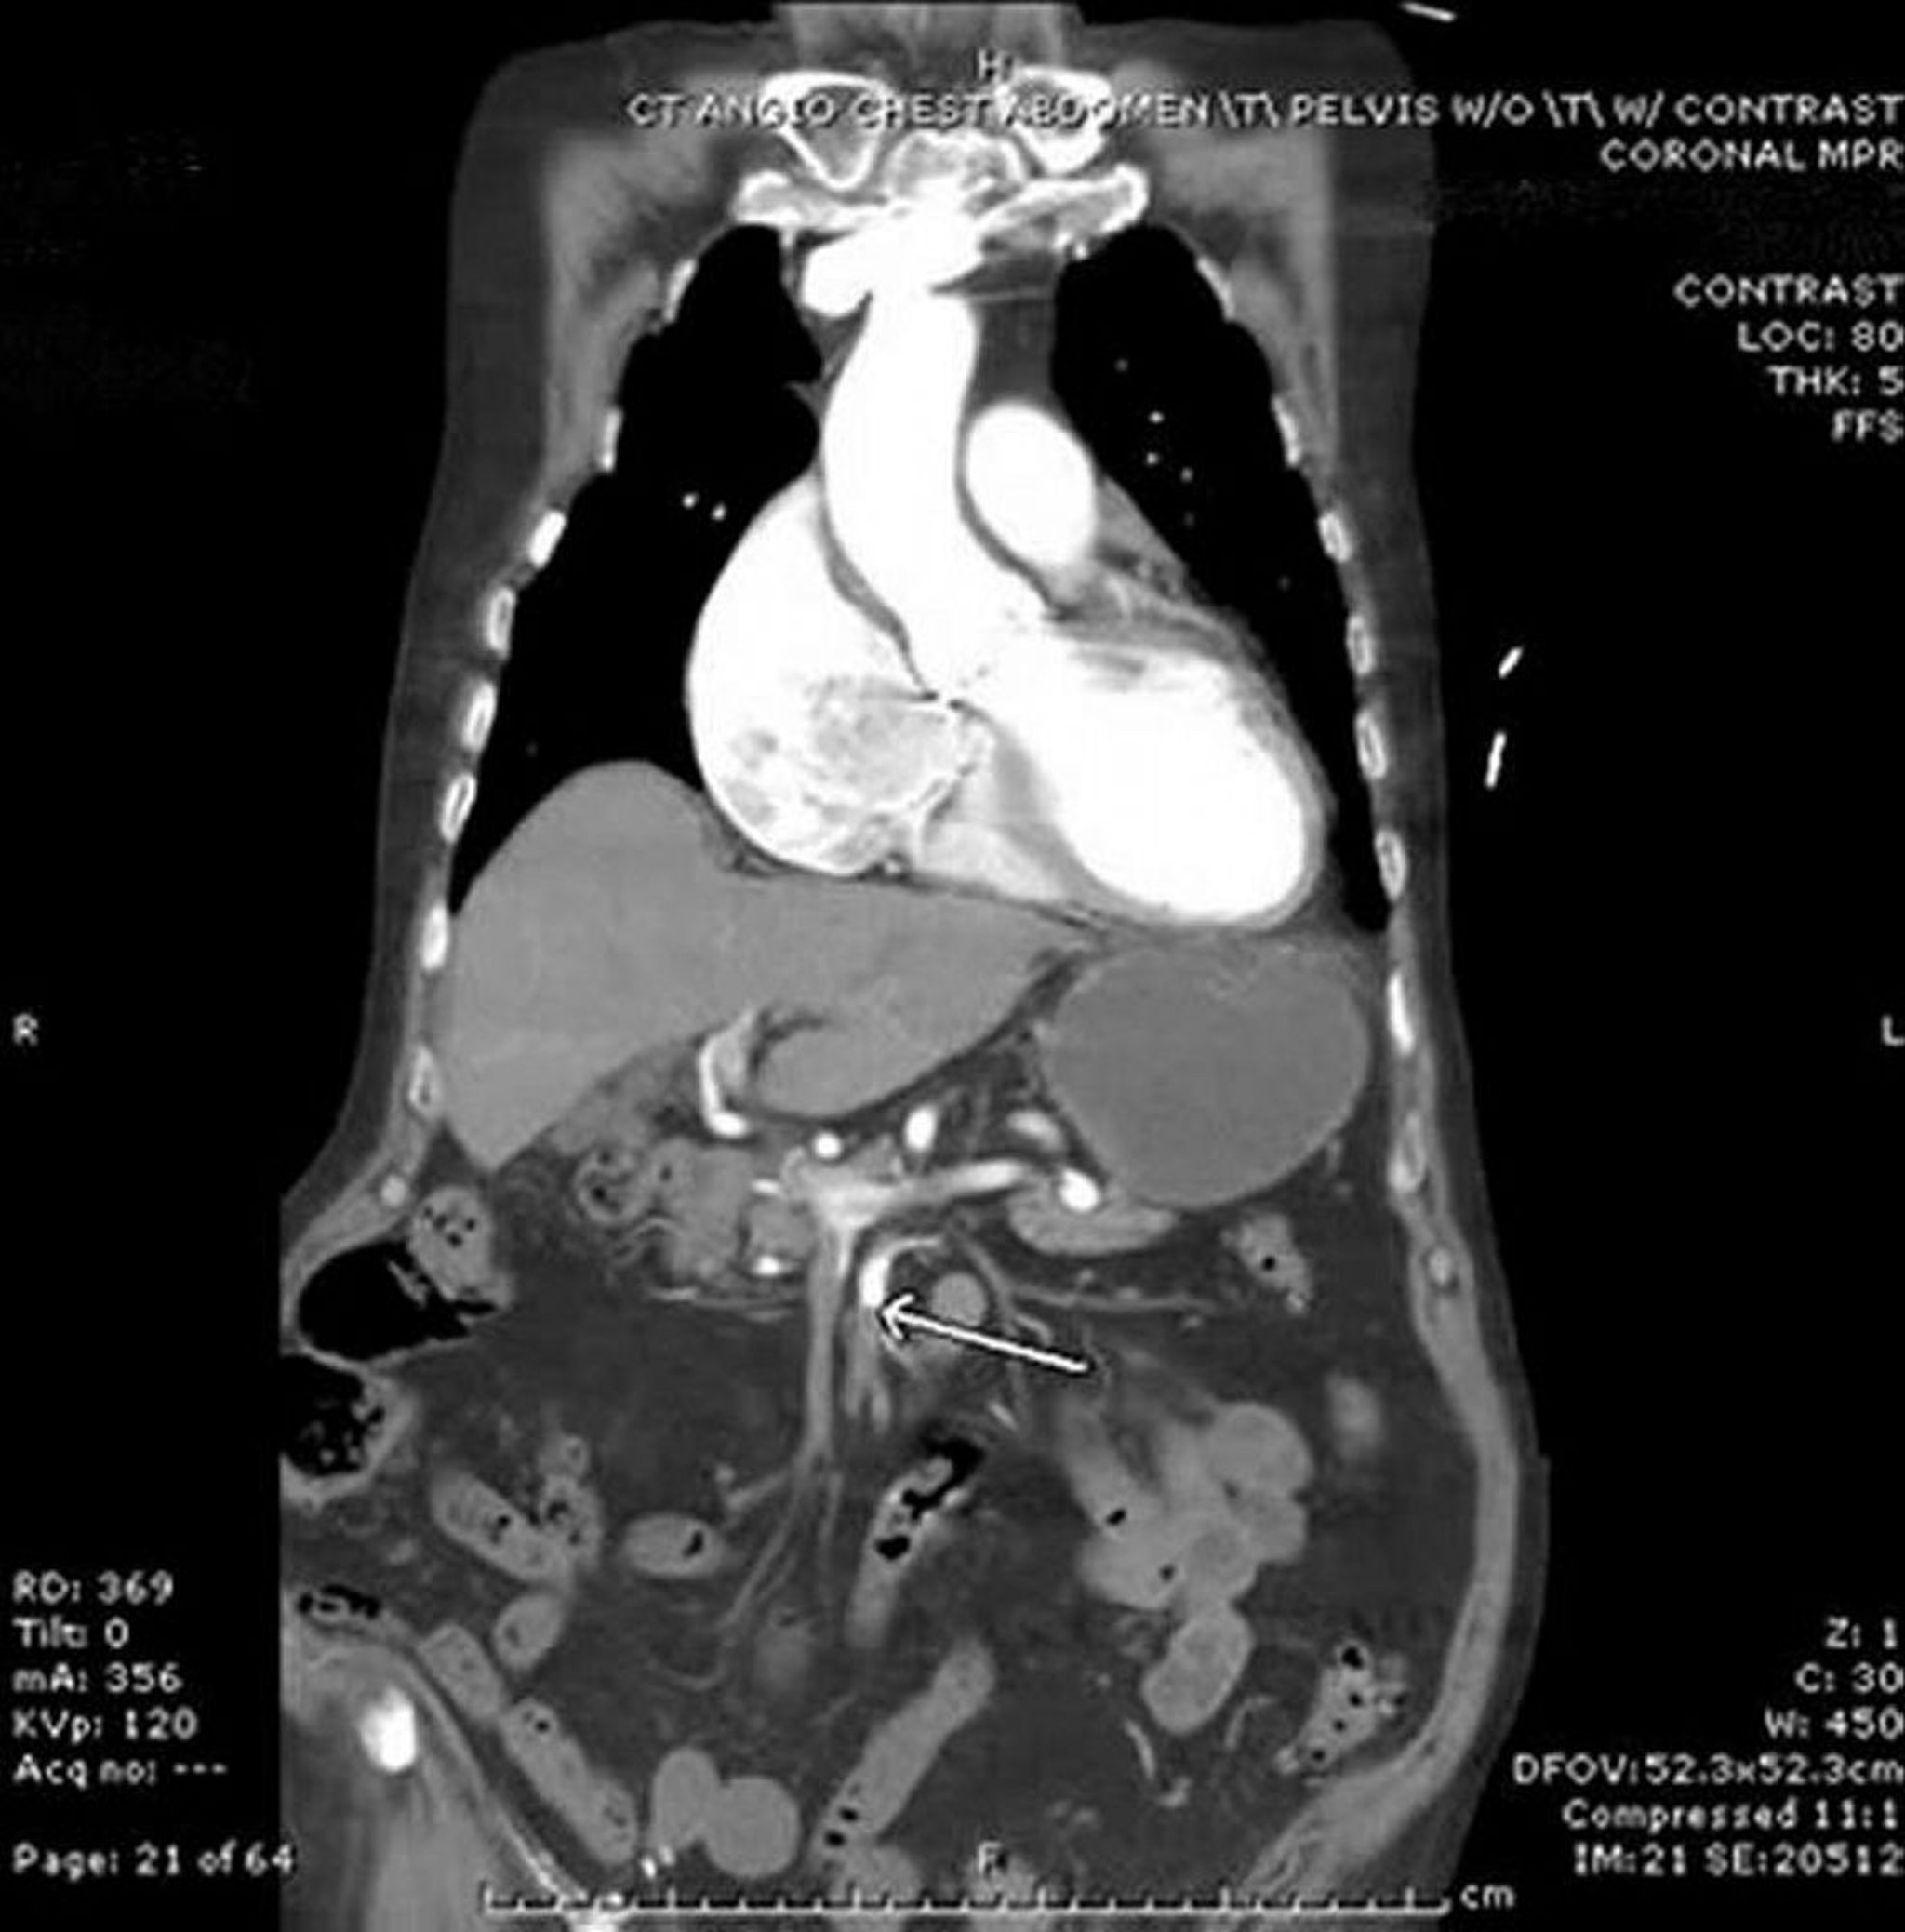

Những bệnh nhân có dấu hiệu phúc mạc rõ ràng nên được đưa thẳng vào phòng mổ để vừa chẩn đoán vừa điều trị. Với các trường hợp khác, chụp chọn lọc mạch mạc treo hoặc chụp CT mạch là thủ thuật chẩn đoán được lựa chọn. Chụp cộng hưởng từ mạch có thể được sử dụng nếu có chống chỉ định với thuốc cản quang tiêu chuẩn đường tĩnh mạch.

Các phương pháp chẩn đoán hình ảnh khác và các chất chỉ điểm trong huyết thanh có thể chỉ ra những bất thường nhưng thiếu độ nhạy và đặc hiệu trong giai đoạn sớm của bệnh, khi mà chẩn đoán là điều quyết định nhất. Các phim chụp X-quang bụng không chuẩn bị chủ yếu hữu ích trong việc loại trừ các nguyên nhân gây đau khác (ví dụ: thủng tạng rỗng), mặc dù khí tĩnh mạch cửa hoặc khí ruột có thể xuất hiện muộn trong quá trình mắc bệnh. Những dấu hiệu này cũng thấy trên CT, cũng có thể nhìn trực tiếp thấy hình ảnh tắc mạch - chính xác hơn là ở bên tĩnh mạch. Siêu âm Doppler đôi khi có thể xác định được tắc động mạch, nhưng độ nhạy thấp. MRI rất chính xác trong trường hợp tắc mạch máu đầu gần nhưng kém chính xác hơn trong tắc mạch máu đầu xa.